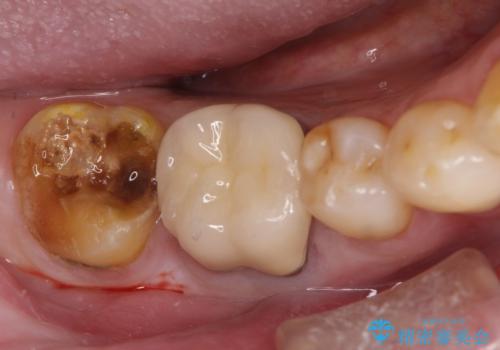

虫歯の治療 オールセラミッククラウン

担当医 河口智英